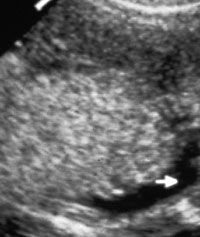

- Mild renal pyelectasis